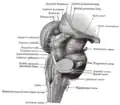

Galerie d'images

Mésencéphale et rhombencéphale (vue postero-latérale).